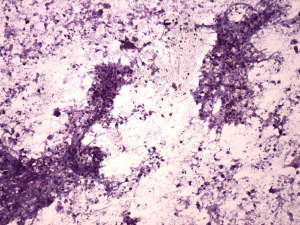

Cytology from the lymph node resulted in metastatic squamous cell carcinoma.

Histopathology disclosed a lymph node metastasis of a basaloid squamous cell carcinoma. The tumor did not spread extracapsular and was HPV-positive. Only one of the 18 removed node contained metastasis.